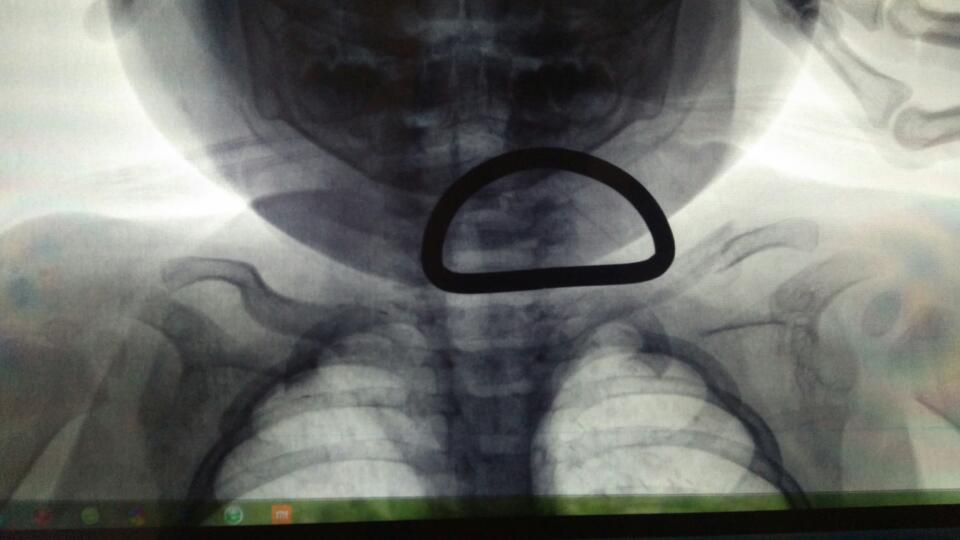

11个月的宝宝不慎从床上掉落,导至左锁骨骨折且上下移位,去医院大夫没有做正骨等任何冶疗,只是给绑了8字背带,五天后复查大夫说背带太松,给重新紧固后拍X片基本对位,回家后感觉太紧,勒痕严重我怕有问题就稍微松了一些,第12天又拍了X光片复查,发现对位不如上一次好,请问专家8字背带的松紧是否会影响锁骨对位?现在对位不良该如何冶疗,谢谢?